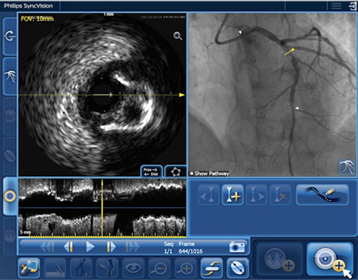

Ко-регистрация со ВСУЗИ позволяет с легкостью измерять длину сосуда, а также площадь/диаметр для точного определения размеров стента. Эта функция также обеспечивает автоматическое одновременное отображение изображений ВСУЗИ и ангиографических изображений в режиме реального времени для сопоставления критически важных анатомических ориентиров, особенно в сложных случаях, например, бифуркациях1,2,3,4

• Помогает вам точно понять границы поражения прямо на ангиограмме.